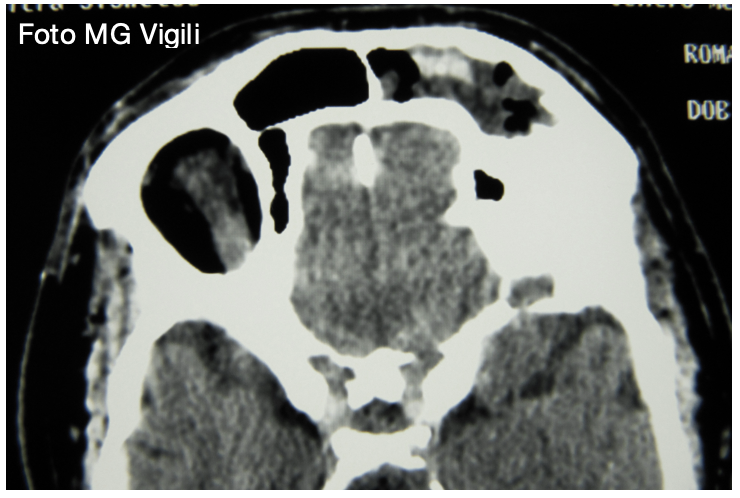

Osteomi dei seni paranasali: il fumo fattore di rischio per la crescita. Esistono dei fattori di rischio che siano potenzialmente associati alla crescita degli osteomi dei seni paranasali?

Uno studio statunitense della Upstate Medical University, Syracuse, NY, USA sul confronto delle immagini longitudinali di 47 pazienti affetti da osteoma dei seni paranasali ha trovato che l’incremento di volume era significativamente maggiore nei pazienti fumatori, pregressi ed attuali, rispetto ai non fumatori.